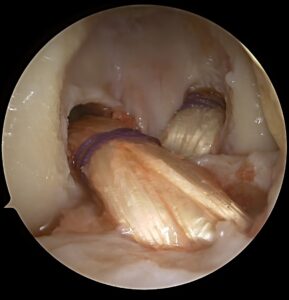

Meniskų susiuvimai, rekonstrukcijos, implantacijos ir transplantacijos.